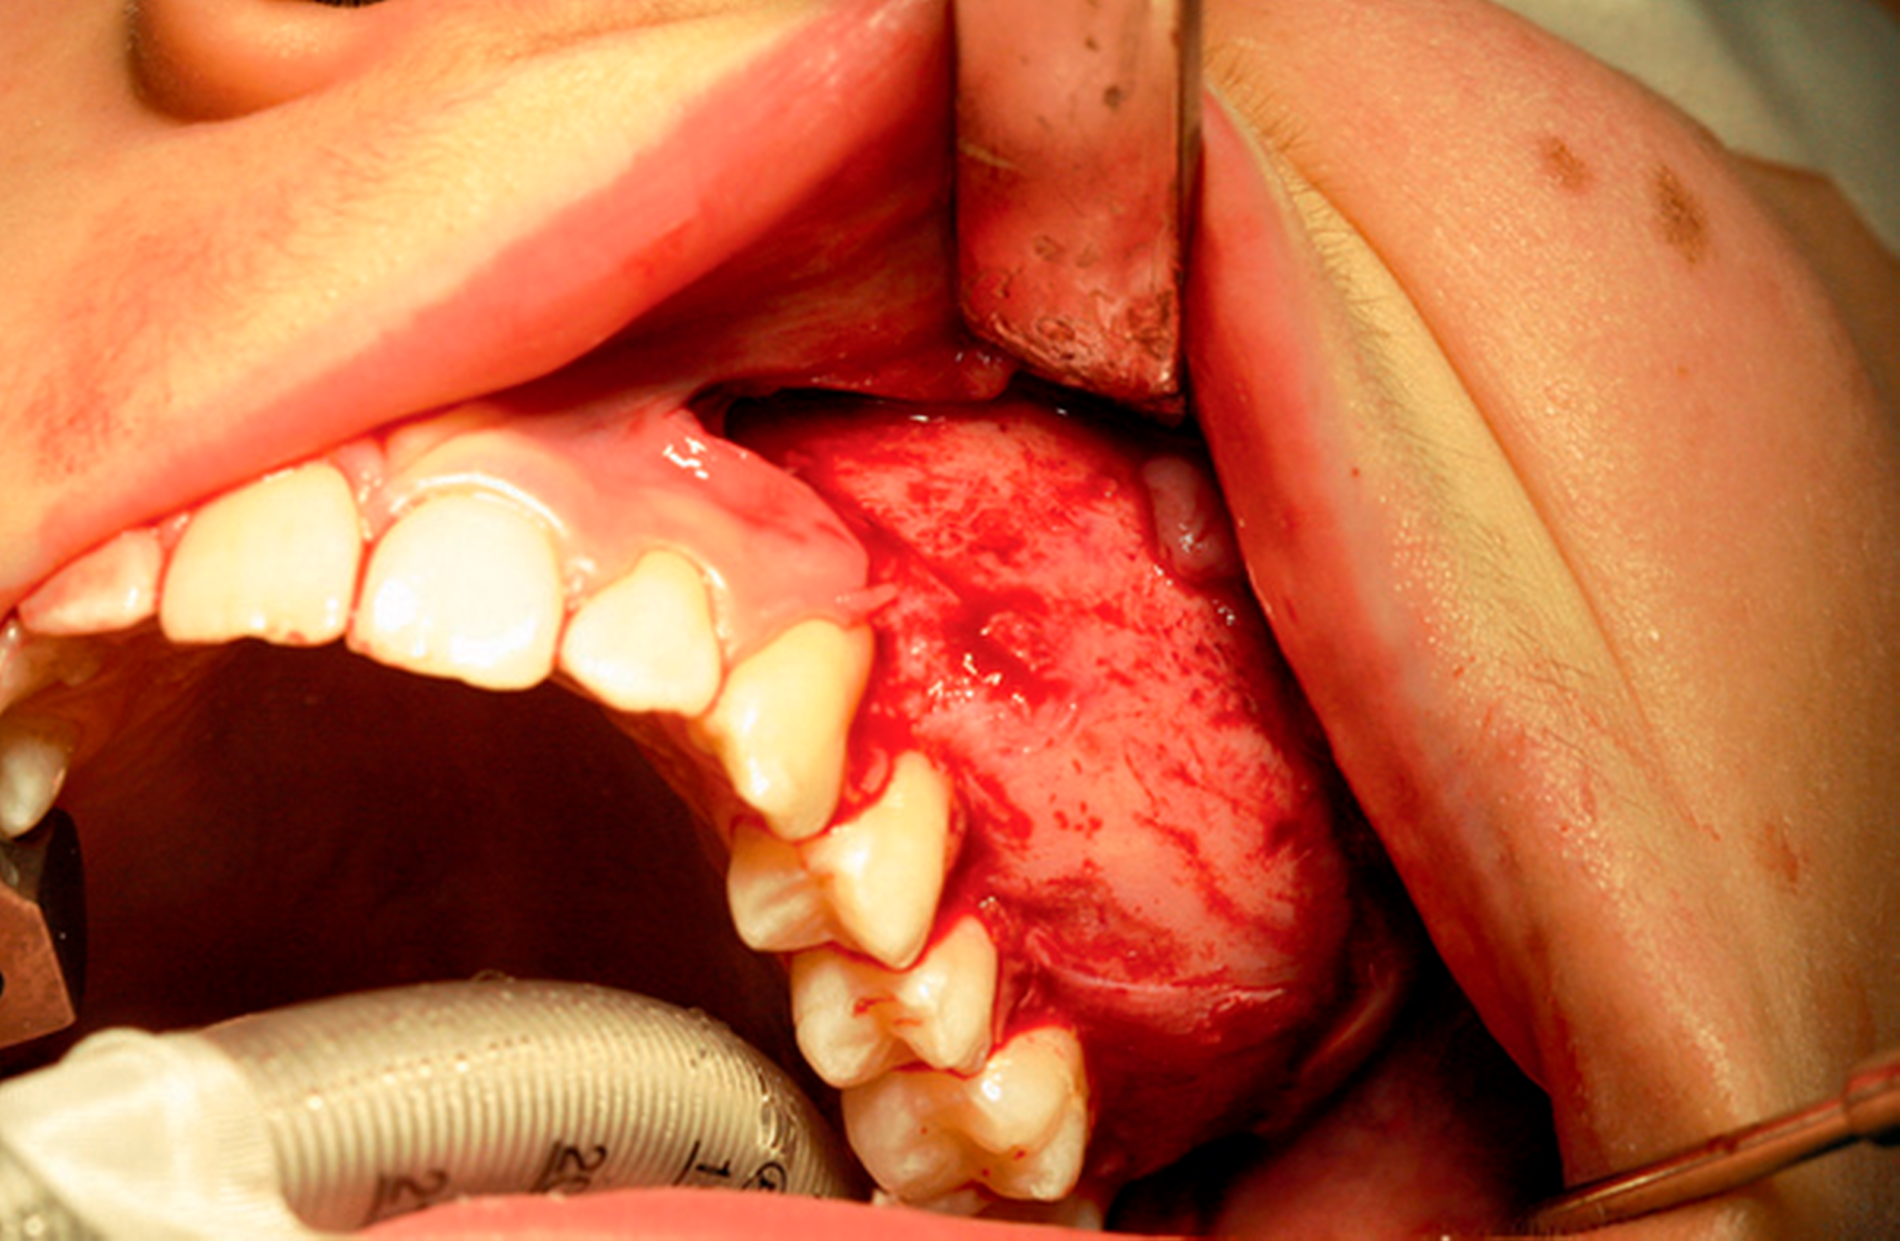

Aufgrund der bestehenden Symptomatik des Patienten wurde die Indikation für ein operatives Vorgehen in oraler Intubationsnarkose gestellt. Gleichzeitig sollten die Weisheitszähne 28, 38, 48 entfernt werden. Nach Narkoseeinleitung wurde ein Lokalanästhetikum mit Adrenalinzusatz 1:200.000 injiziert (Abbildung 4a).

Anschließend folgte die marginale Schnittführung von 27 bis 23 mit jeweils zwei vertikalen Entlastungsschnitten. Nach Bildung des Mukoperiostlappens und Darstellung des Nervus infraorbitalis erfolgte die Abtragung der fibrösen Dysplasie unter Schonung der Zahnwurzeln und des Nervus infraorbitalis (Abbildungen 4b und 4c). Die Weisheitszähne 28, 38 und 48 wurden ebenfalls entfernt. Bei Zahn 28 kam es dabei zu einer Mund-Antrum-Verbindung, die plastisch gedeckt wurde. Das entnommene Hartgewebe wurde zur histopathologischen Beurteilung ins Knochentumor-Referenzzentrum und DÖSAK-Referenzregister nach Basel (Prof. Dr. Baumhoer) geschickt.